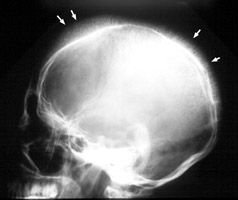

Two lateral skull x-rays with peculiar thin, fine linear extensions radiating out from the skull, appearing as hair standing 'on-end' from the skull. The ‘hair’ represents the accentuated trabeculae extending between the inner and outer skull tables in the expanded diploic marrow spaces. It appears to be ‘on end’ because the trabeculae are oriented perpendicular to the inner and outer tables of the skull. The term is now classically associated with the radiographic changes seen in hemolitic anemia. A. Sickle cell disease. B. Thalassemia.

- Click on the image for a larger versionA - Click on the image for a larger versionB